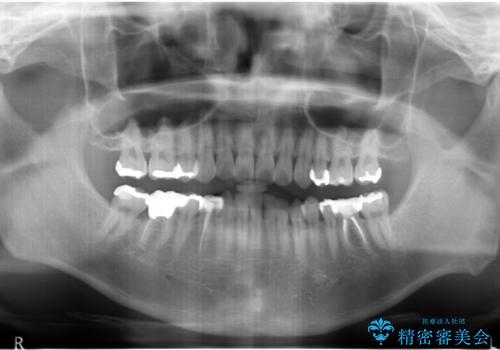

- 全体を見て欲しいと来院。

右下の奥歯の虫歯が大きく、やりかえが難しい状態でした。

右下7については、遠心の歯の高さがなく、また、同様に歯肉縁下にカリエスがあったため、手術を行い改善しました。

- 右下567ブリッジ:43万円(ジルコニアクラウン10万円x3、仮歯1万円x3、APF10万円)、右下4:10万円(emaxクラウン7万円、仮歯1万円、ファイバーコア2万円)(税別)費用は治療当時の料金となります